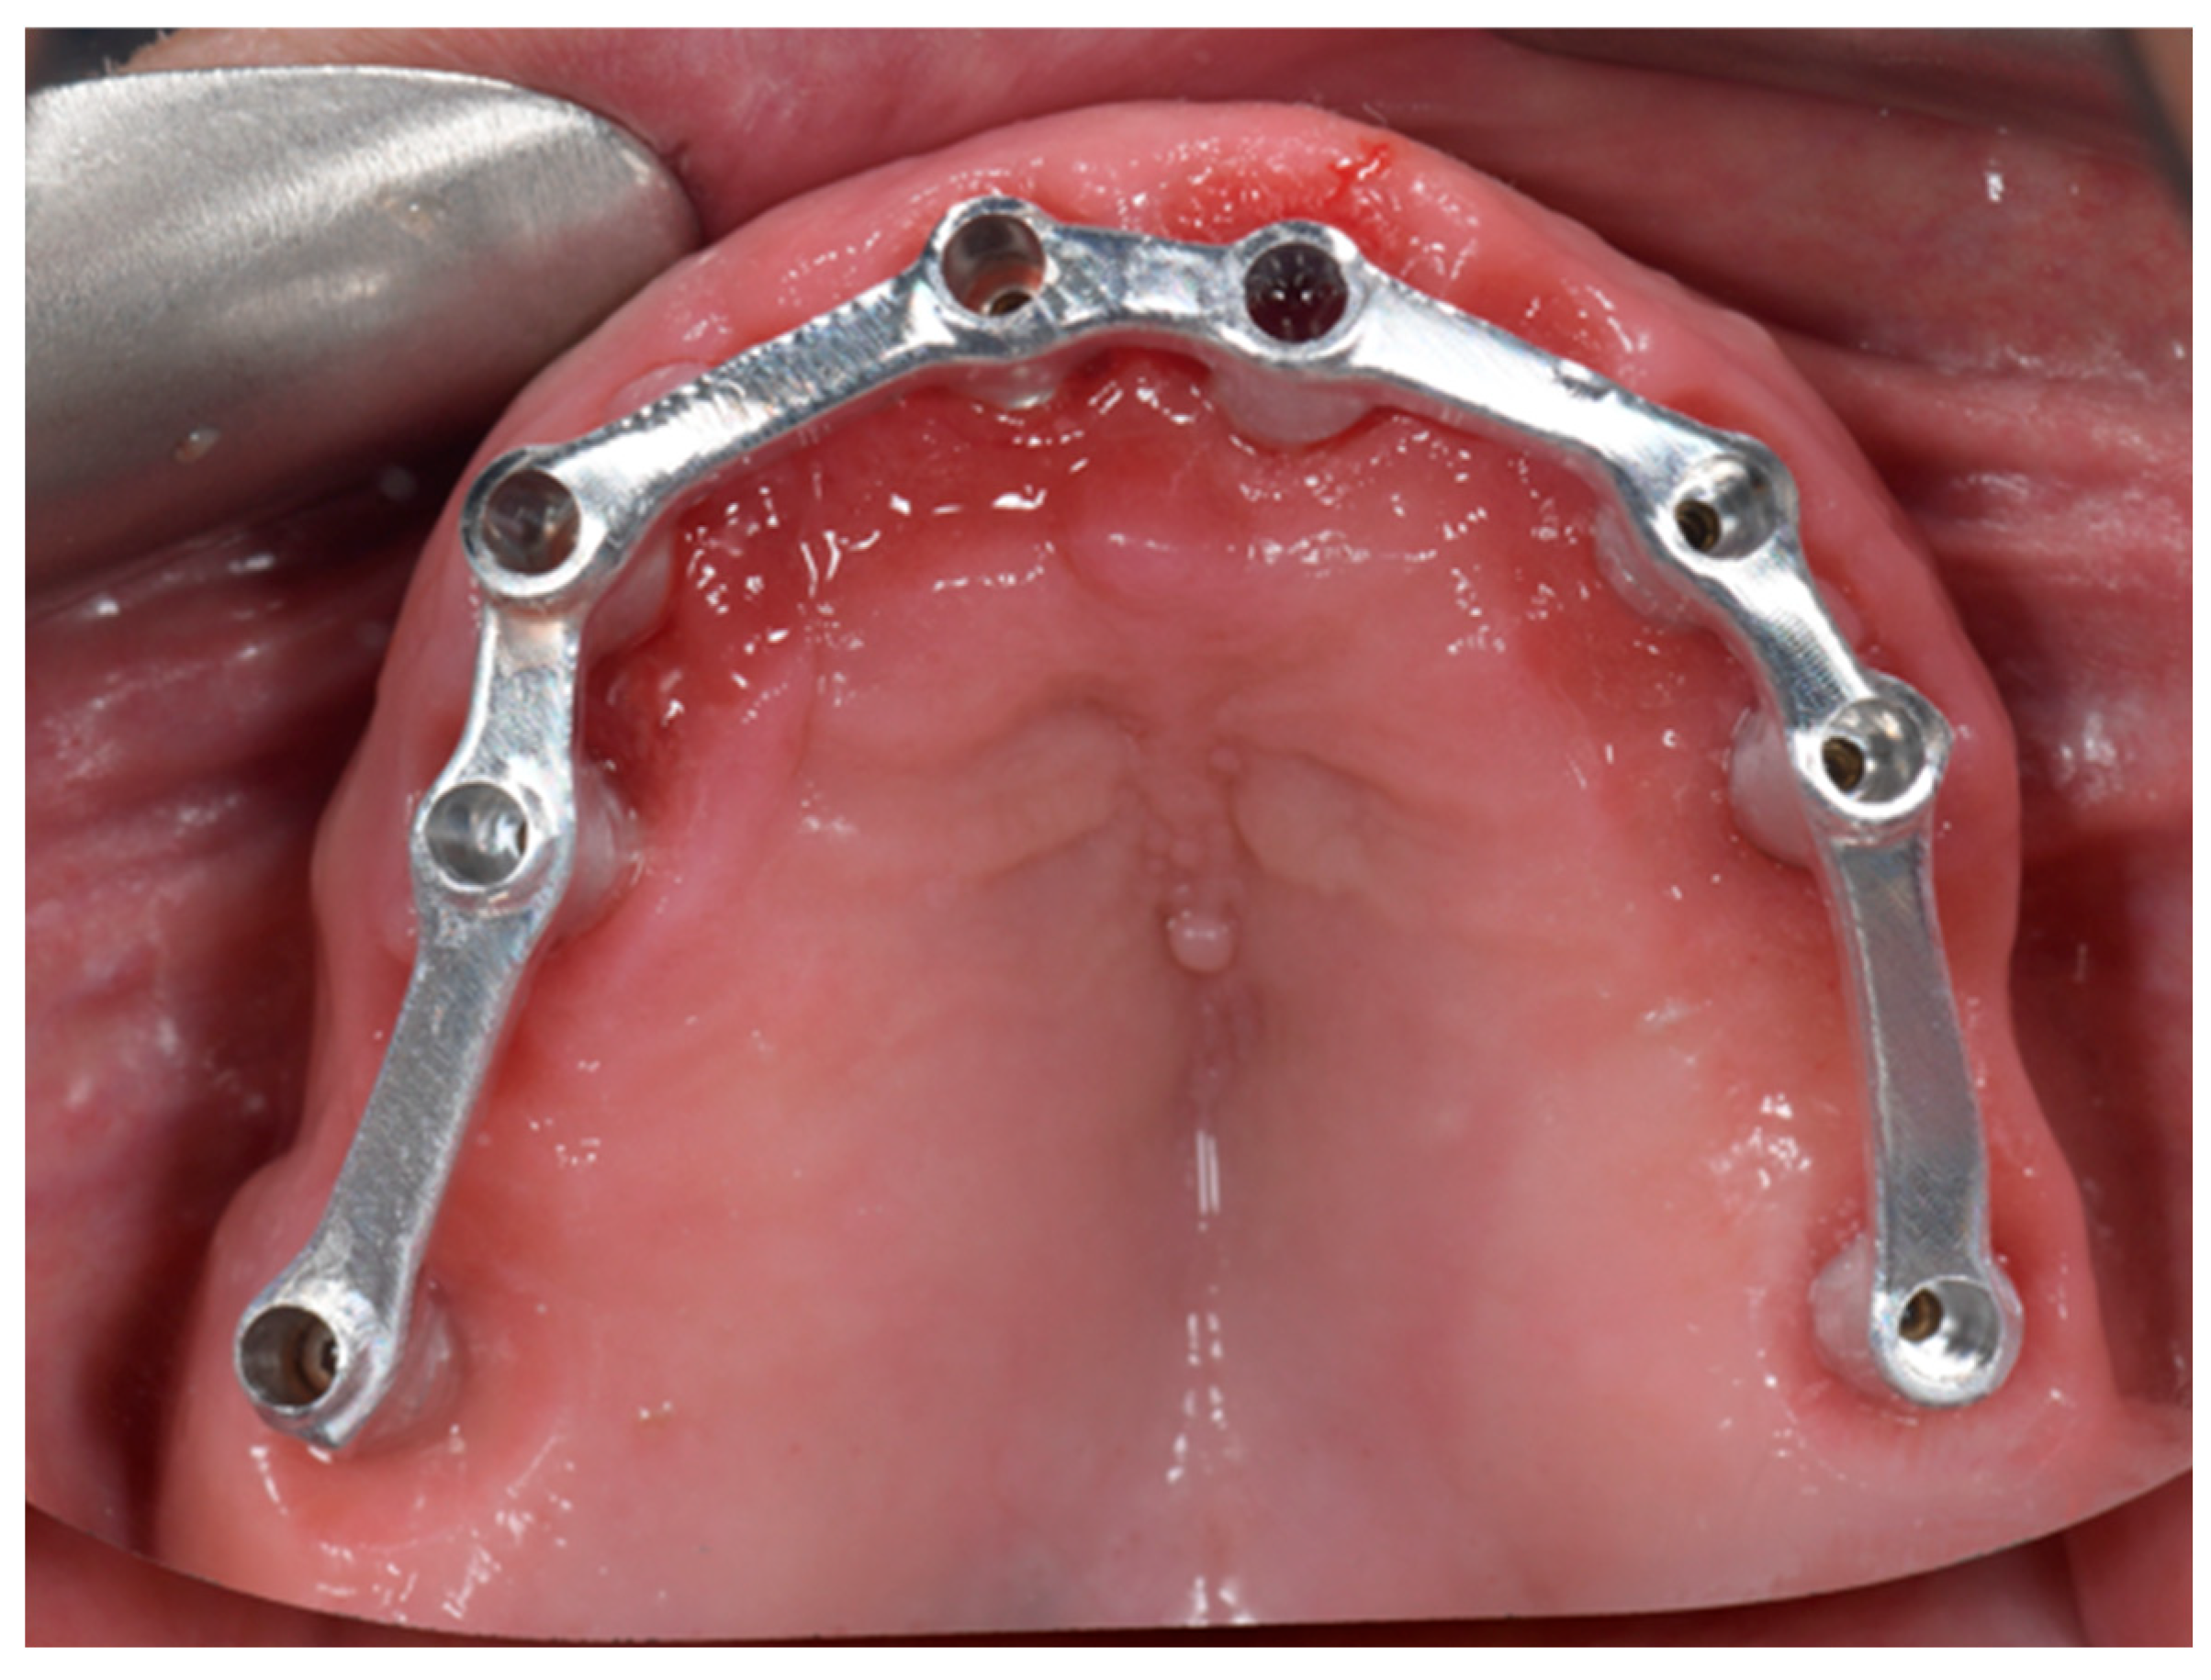

Following definitive impression acquisition, a milled metal verification bar was fabricated and clinically/radiographically evaluated (Figure 2).

Figure 2. Fabrication and clinical evaluation of a CAD/CAM milled metal verification bar following definitive impression acquisition.